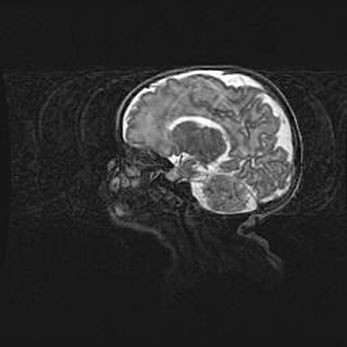

Сообщающаяся гидроцефалия. Кистозная энцефаломаляция головного мозга.

Возраст: 3 месяца 4 дня

Вес: 3100 г

Пол: женский

Окружность головы: 34 см

Срок гестации: 31 неделя

Кистозная энцефаломаляция головного мозга - одна из форм поражения головного мозга в детском возрасте. Характеризуется возникновением множественных и распространённых кист в коре, белом веществе и подкорковых образованиях головного мозга у плодов, новорождённых и детей раннего возраста. Развитие кистозной энцефаломаляции связано с внутриутробной асфиксией и гипотонией, родовой травмой, тромбозом синусов, пороками развития сосудов, инфекциями, сепсисом и другими причинами. Наиболее значимые инфекционные агенты: вирусы простого герпеса, цитомегалии, краснухи, токсоплазмы, энтеробактерии, золотистый стафилококк и другие.